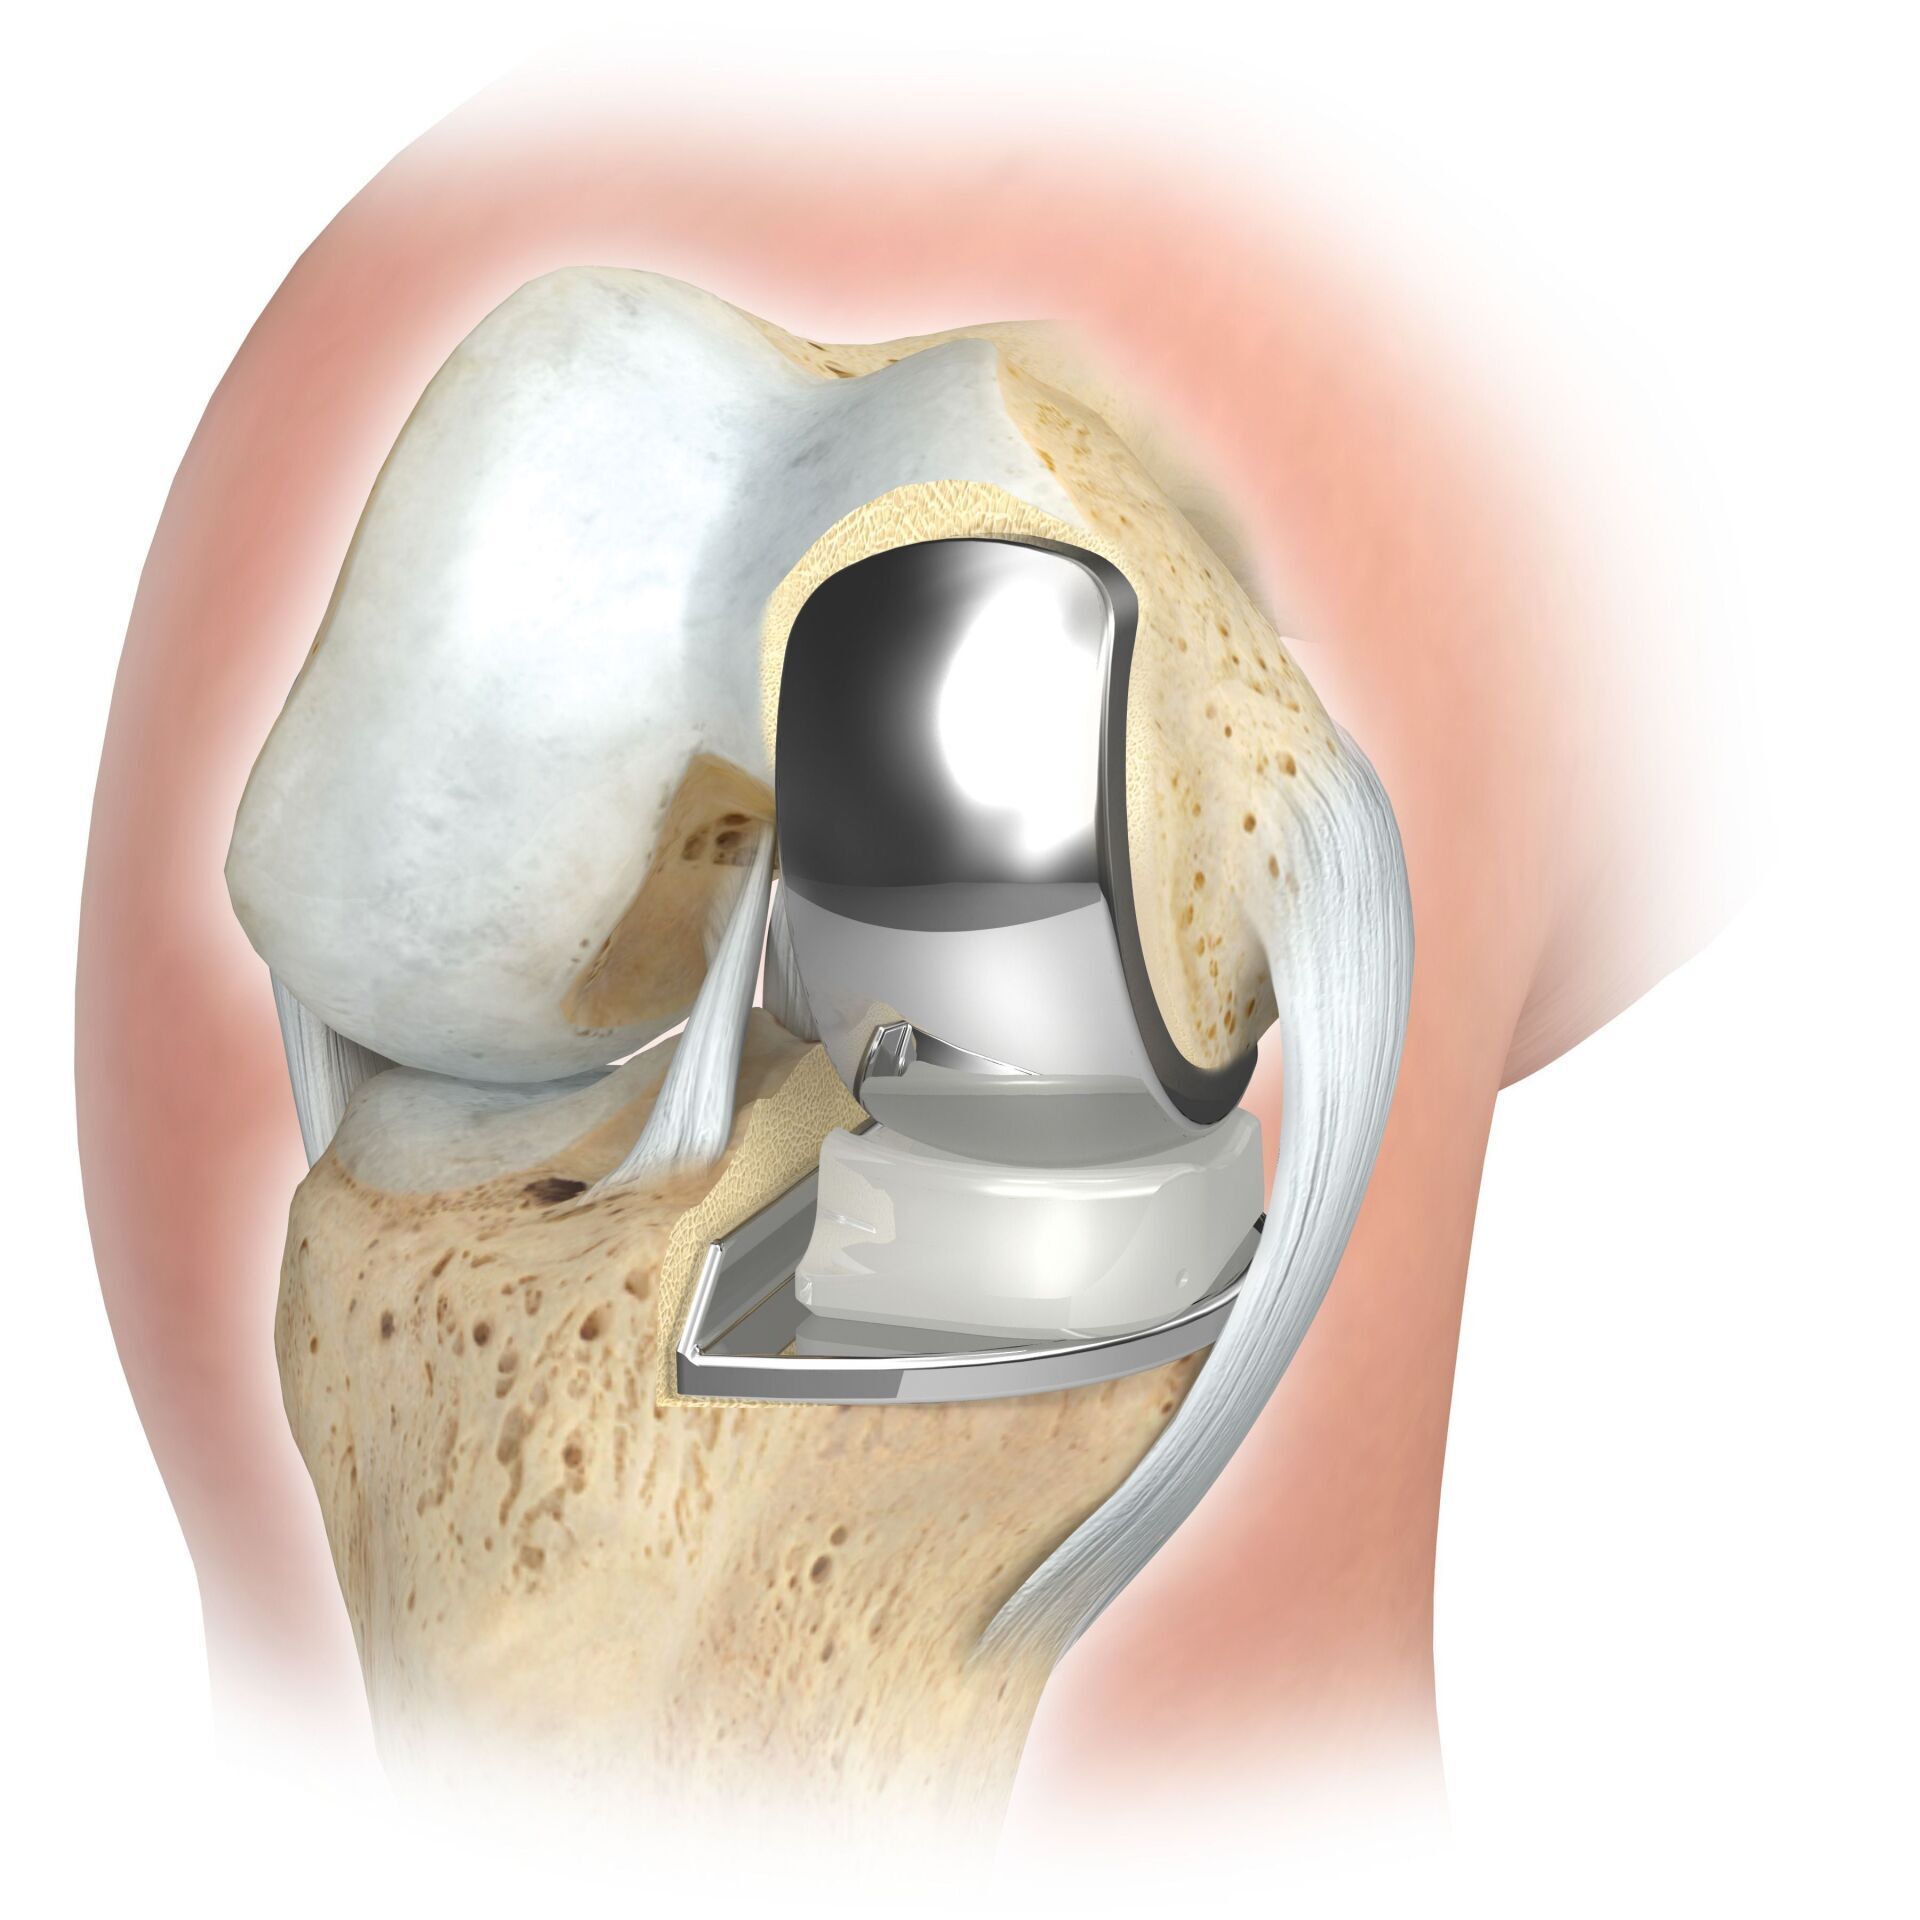

يحل مفصل الركبة الاصطناعي محل سطح الغضروف الذي دمره التهاب المفاصل العظمي. يظل العظم الأساسي في عظم الفخذ والرأس الظنبوبي سليمًا. يقارن البعض مفصل الركبة الاصطناعي الحديث بتتويج الأسنان؛ والمصطلح الدقيق هو ما يسمى بإعادة تسطيح اللقمتين. بين الأسطح الجديدة في الجزء العلوي والسفلي من الساق يوجد ما يسمى بالبطانة المصنوعة من البلاستيك الأبيض المقوى خصيصًا، والتي يمكن رؤيتها في صورة الأشعة السينية على أنها المسافة بين الأجزاء المعدنية.